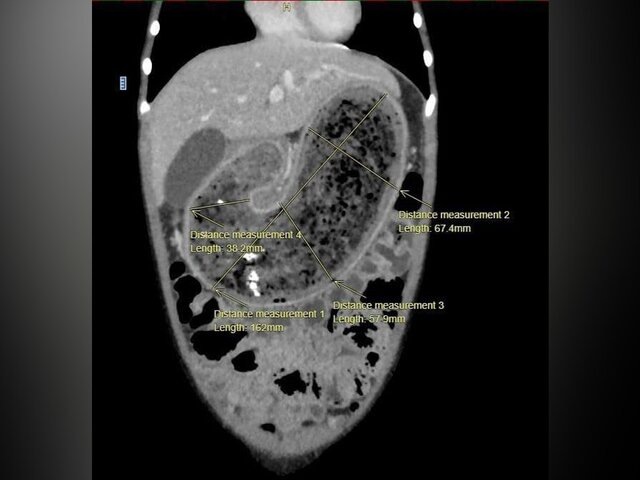

Врачи НИИ неотложной детской хирургии и травматологии – клиники доктора Рошаля – извлекли из желудка 8-летнего ребенка гигантский трихобезоар – комок волос, сообщило медучреждение в телеграм-канале. Девочка поступила в клинику с жалобами на приступы тошноты, рвоту и полный отказ от еды. Мама ребенка обратила внимание врачей на значительное снижение веса дочери – за последние месяцы девочка похудела на 4 килограмма. Во время первичного осмотра медики обнаружили заметное образование, выпирающее на передней стенке желудка. Проведенная компьютерная томография подтвердила наличие огромного трихобезоара, который полностью заполнил желудок, двенадцатиперстную кишку и начальный отдел тонкой кишки. Как пояснили в клинике, небольшие трихобезоары, которые находятся в желудке, можно удалить эндоскопическим методом. Однако в этом случае потребовалась операция. Лечащий врач Анастасия Коновалова рассказала, что операция проводилась бригадой врачей под руководством хирурга Рубена Налбандян. Она включа